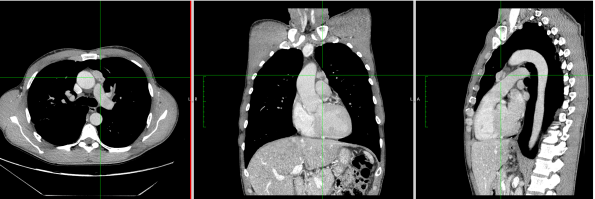

1. CT-Scan and PET-Scan

A 47-year-old male patient with no previous medical history was referred to the institution with a diagnosis of mediastinal mass suspected of being thymoma, without any clinical or laboratory signs of myasthenia gravis. The chest CT-scan showed a 2.5 cm lesion with no clear signs of infiltration of surrounding tissues and with a PET uptake of SUV max 4. The patient was scheduled for subxiphoid bilateral robotic-assisted thymectomy.